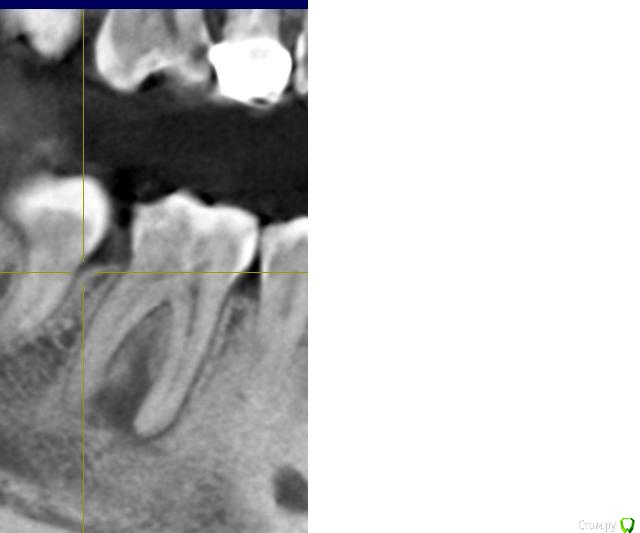

Ксения_ Опубликовано 27 августа, 2015 Поделиться Опубликовано 27 августа, 2015 (изменено) Здравствуйте Уважаемые Доктора! КТ сделано 4 мес назад. После этого пролечен кариес 14, 16, 37, 35. Пролечен пульпит 25, 36.Осталось пролечить пульпит в 15, 26, 47. Удалить все восьмерки.Далее ортодонтия. Стоит вопрос об удалении 46. Зуб ранее был пролечен другим врачом некачественно (+ пропущен канал).Мой лечащий доктор, после консультаций с коллегами, предлагает удаление, т.к. с его слов прогноз у этого зуба неблагоприятный (считает, что через пару лет процесс повторится) и смысла в столь дорогом лечении нет. Мне, конечно, хотелось бы по возможности зуб сохранить.Как вы считаете какой прогноз у этого зуба? P.S. Зуб не беспокоит. Точнее ни один зуб у меня вообще ни разу в жизни не болел (несмотря на такое количество пульпитов, которые для меня были неожиданностью. Врачу своему доверяю.). Несколько докторов которые меня смотрели считают, что у меня высокий болевой порог. Изменено 27 августа, 2015 пользователем Ксения_ Ссылка на комментарий

M@estro Опубликовано 27 августа, 2015 Поделиться Опубликовано 27 августа, 2015 (изменено) Судя по рентгену - прогноз благоприятный. Зуб сохранен,это главное. "процесс повторится" - на это при современном подходе выделяют не более 5 % .Если бы у меня 95 % вероятности в казино было - я бы дом поставил , не то что зуб полечил ) Ключевое при перелечивании - соблюдение современного протокола лечения. P.s. После лечения уже больше двух лет прошло,недавно был на осмотре - процесс все никак не повторится )) Изменено 27 августа, 2015 пользователем M@estro 3 Ссылка на комментарий

Чертков Александр Опубликовано 28 августа, 2015 Поделиться Опубликовано 28 августа, 2015 Согласен с M@estro, однозначно лечить. Прогноз хороший! 1 Ссылка на комментарий